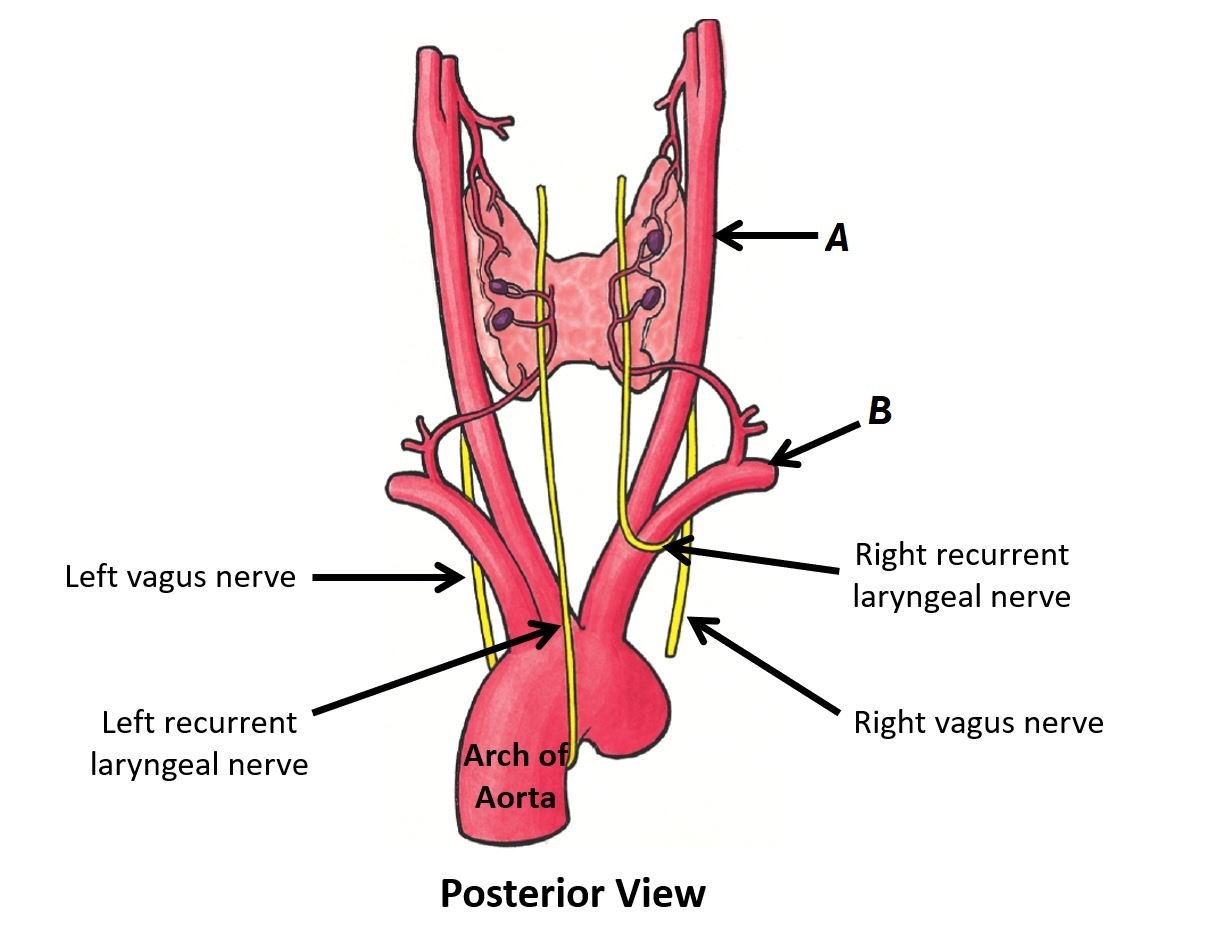

Name vessels A and B

A - Right common carotid artery

B - Right subclavian artery